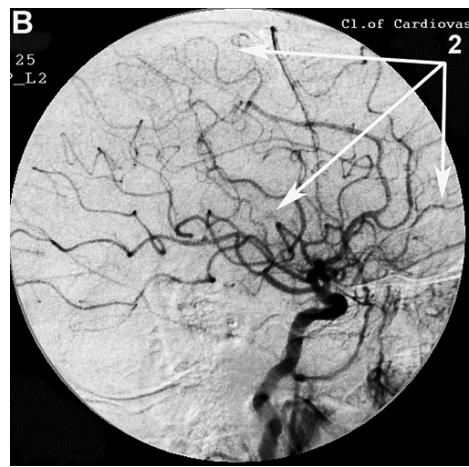

After transcatheter intracerebral laser PBMT, according to digital MUGA, all 48 (100%) patients showed a direct positive result manifested in pronounced angiogenesis, collateral and capillary revascularization, reduction of arteriovenous shunts, as well as an improvement in venous outflow (Figures 1A, 1B, Figures 2A, 2B).

Figure 2: Patient P., 75 years old, female. Medical history of AD - 12 years, TDR-3.

A. Left internal carotid artery angiogram, arterial phase, before transcatheter Intracerebral laser PBMT: 1. hypovascular areas in temporal and frontoparietal regions; B. Left internal carotid artery angiogram, arterial phase, after transcatheter Intracerebral laser PBMT: 2. stimulation of angiogenesis, restoration of collateral and capillary blood supply in the temporal and frontoparietal regions.